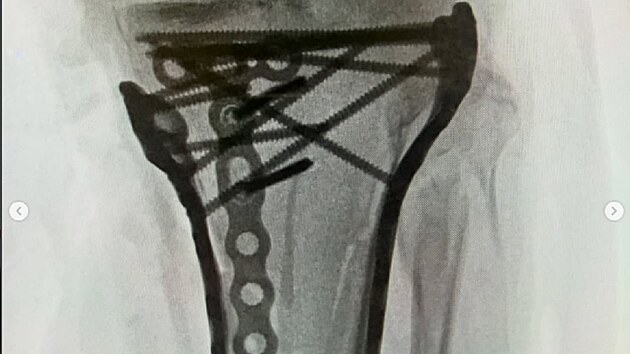

Dvojnásobná mistryně světa při pádu v Cortině d’Ampezzo utrpěla komplexní zlomeninu holenní kosti. V Trevisu absolvovala postupně čtyři operace, v pondělí odletěla do Ameriky, kde se nyní podrobila dalšímu zákroku.